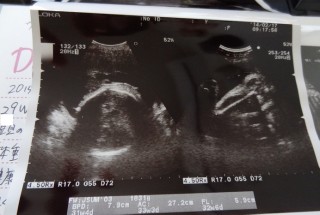

32週2日検診行ってきました☆

赤ちゃんは約2100gでちょい大きめ☆

前回より頸管長くなってたけど

張りが強いから急遽NST(;_;)

なんとかギリギリ入院は回避できたけど

相変わらず子宮口は柔らかく

内子宮口を赤ちゃんが頭でガンガン押してるから

引き続き安静との事。゜+(。ノдヽ。)゜+。

あと4週間はお腹でもたせてねと言われました